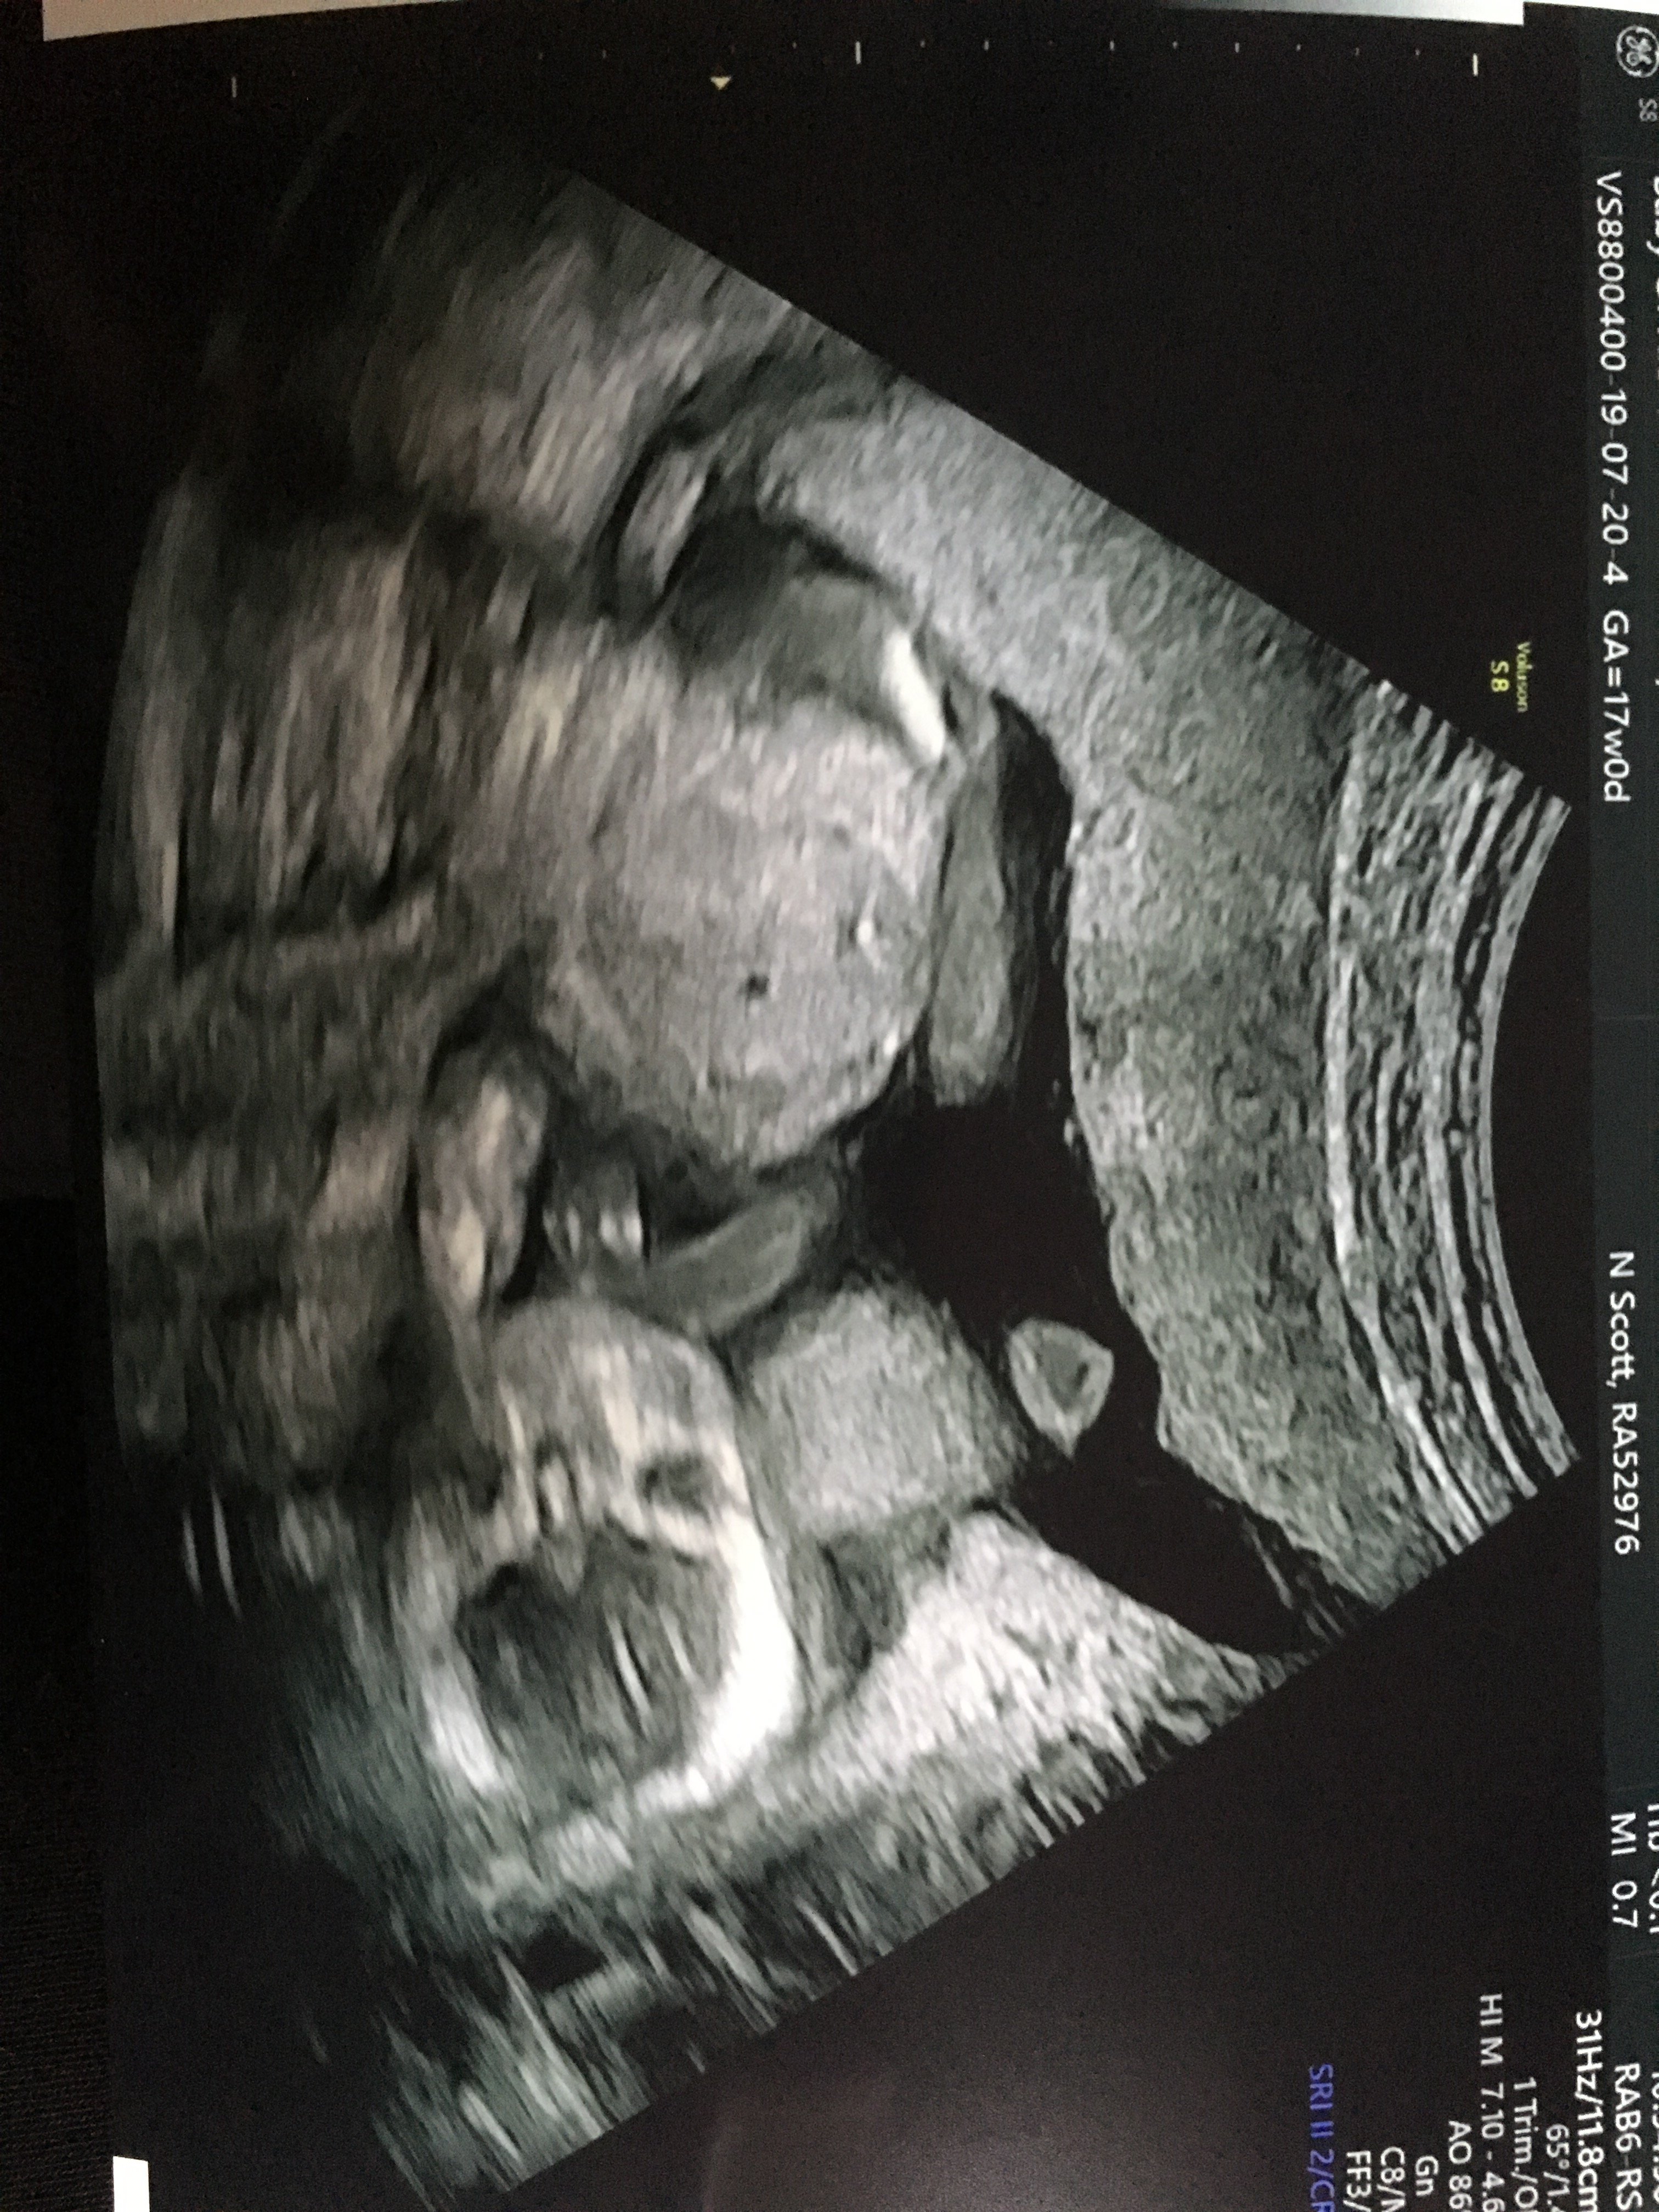

Od dziś czuję ruchy. To moja druga ciąża wiec brzuch mam duży 15 +5tc Zobacz załącznik 1000349